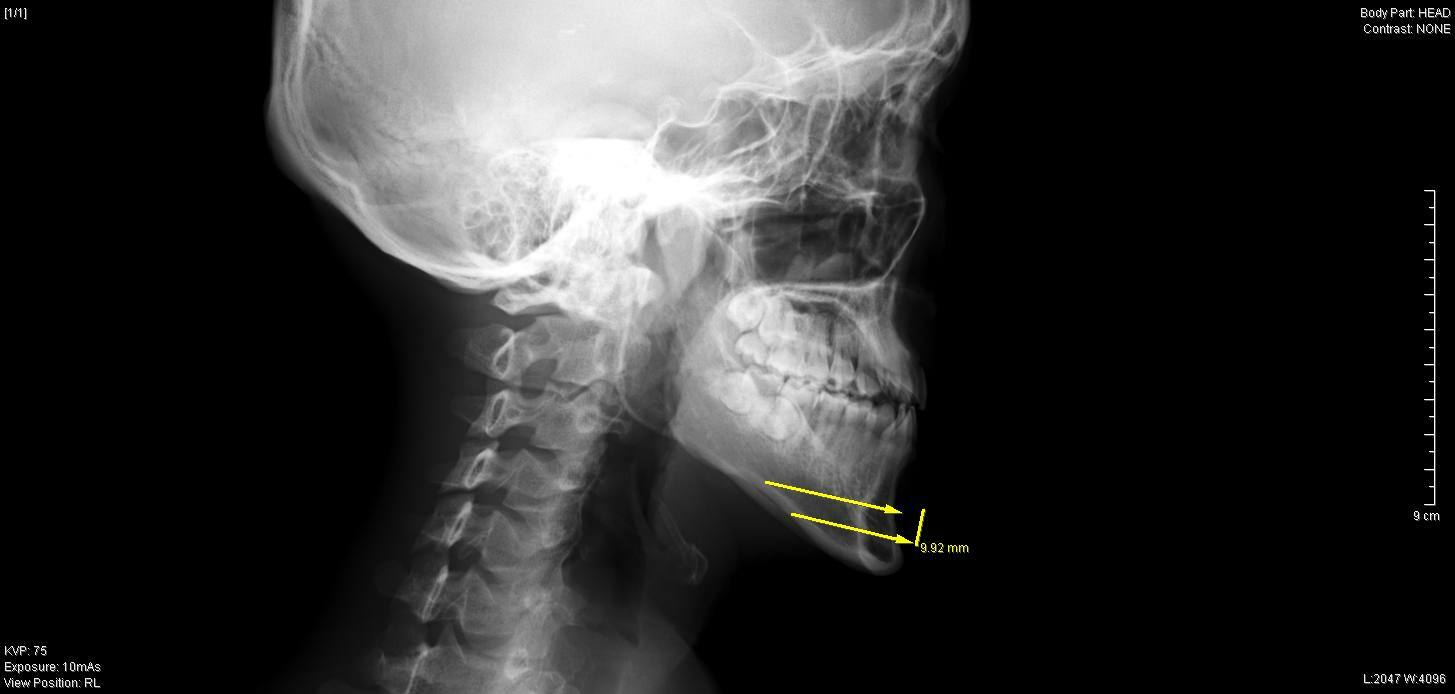

今回の症例では、最大9mm幅で下顎骨を中抜きし、

おとがい先端を約4mm前進させて

チタンスクリュー、プレートで再接合しました。

今回の症例では、下顎骨が長い割に

オトガイ神経の位置がかなり下側に開口しており、

骨切りの際、右側のオトガイ神経に少しダメージを与えてしまいましたが、

2

週間後の抜糸では、

鈍麻は残るものの知覚に左右差なく順調に回復していました。